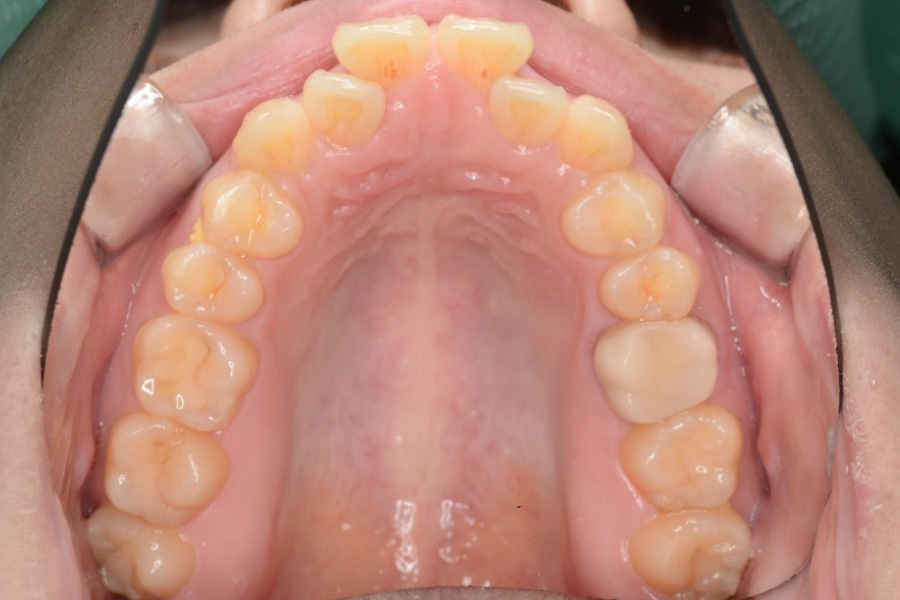

【20代女性】

歯のガタつき、突出感を

インビザライン矯正で治療したケース

治療前

主訴 歯のガタつき、突出感が気になる

治療内容 インビザライン矯正

小臼歯抜歯